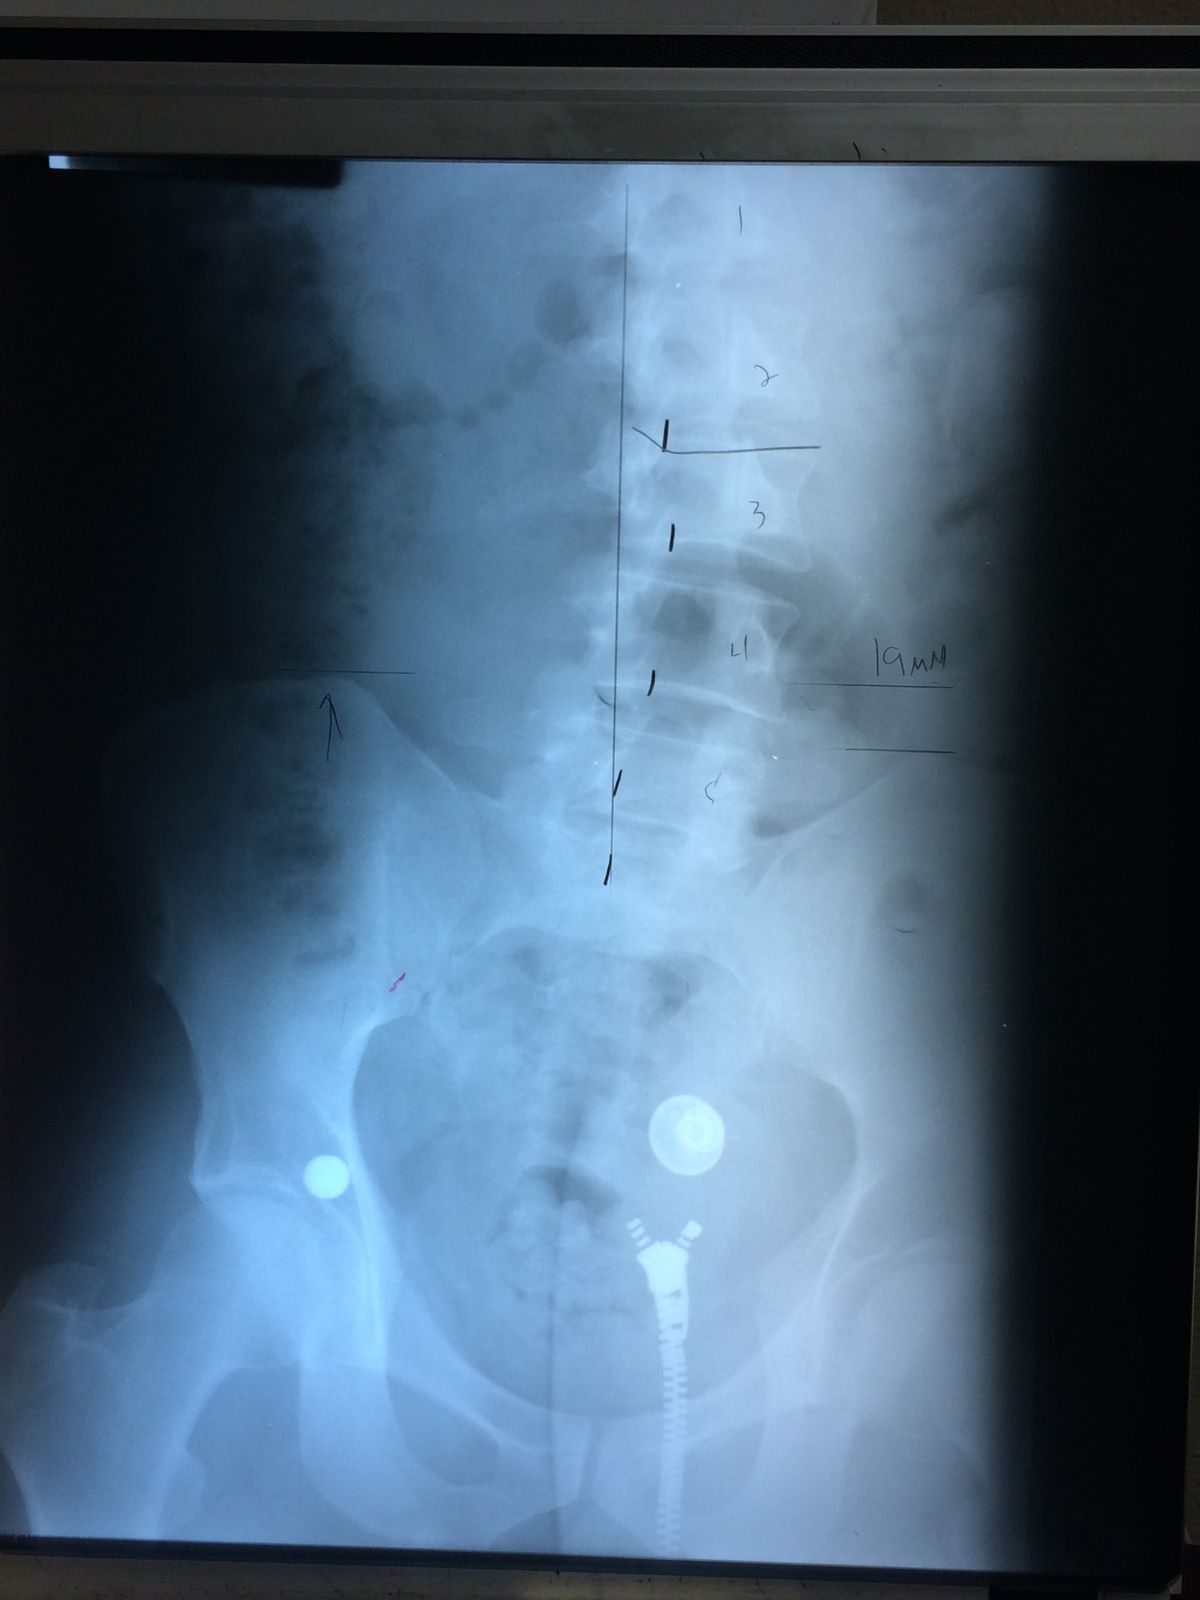

Visits to healthcare professionals revealed the unwelcome diagnosis of right convex lumbar scoliosis, a condition where the spine curves sideways.

If you were to stand in front of me and look at me with X-ray vision, you’d see that my lower back (the lumbar region) curves to my right instead of being vertical.

This condition was a direct consequence of my altered posture due to the leg length discrepancy.